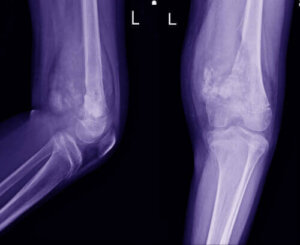

Diagnosen stilles vanligvis på grunnlag av et klinisk intervju og helsehistorie, sammen med noen tester. Det starter vanligvis med røntgenbilder, som suppleres med en MR. En lege vil bestille en biopsi så snart de oppdager et problem og identifiserer området.